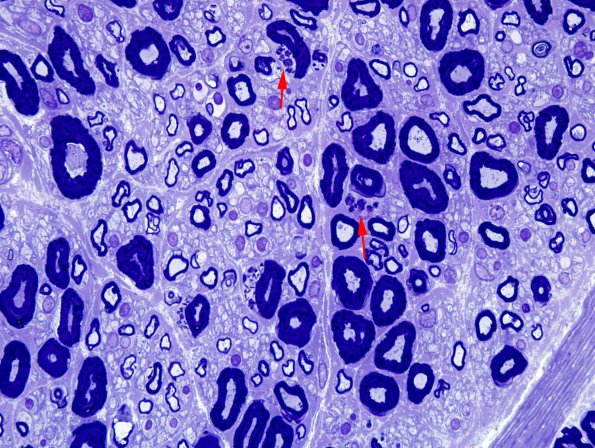

1A1,2 Several Schwann cells of large myelinated axons contain multiple Pi granules. (One micron thick toluidine blue stained plastic embedded section)